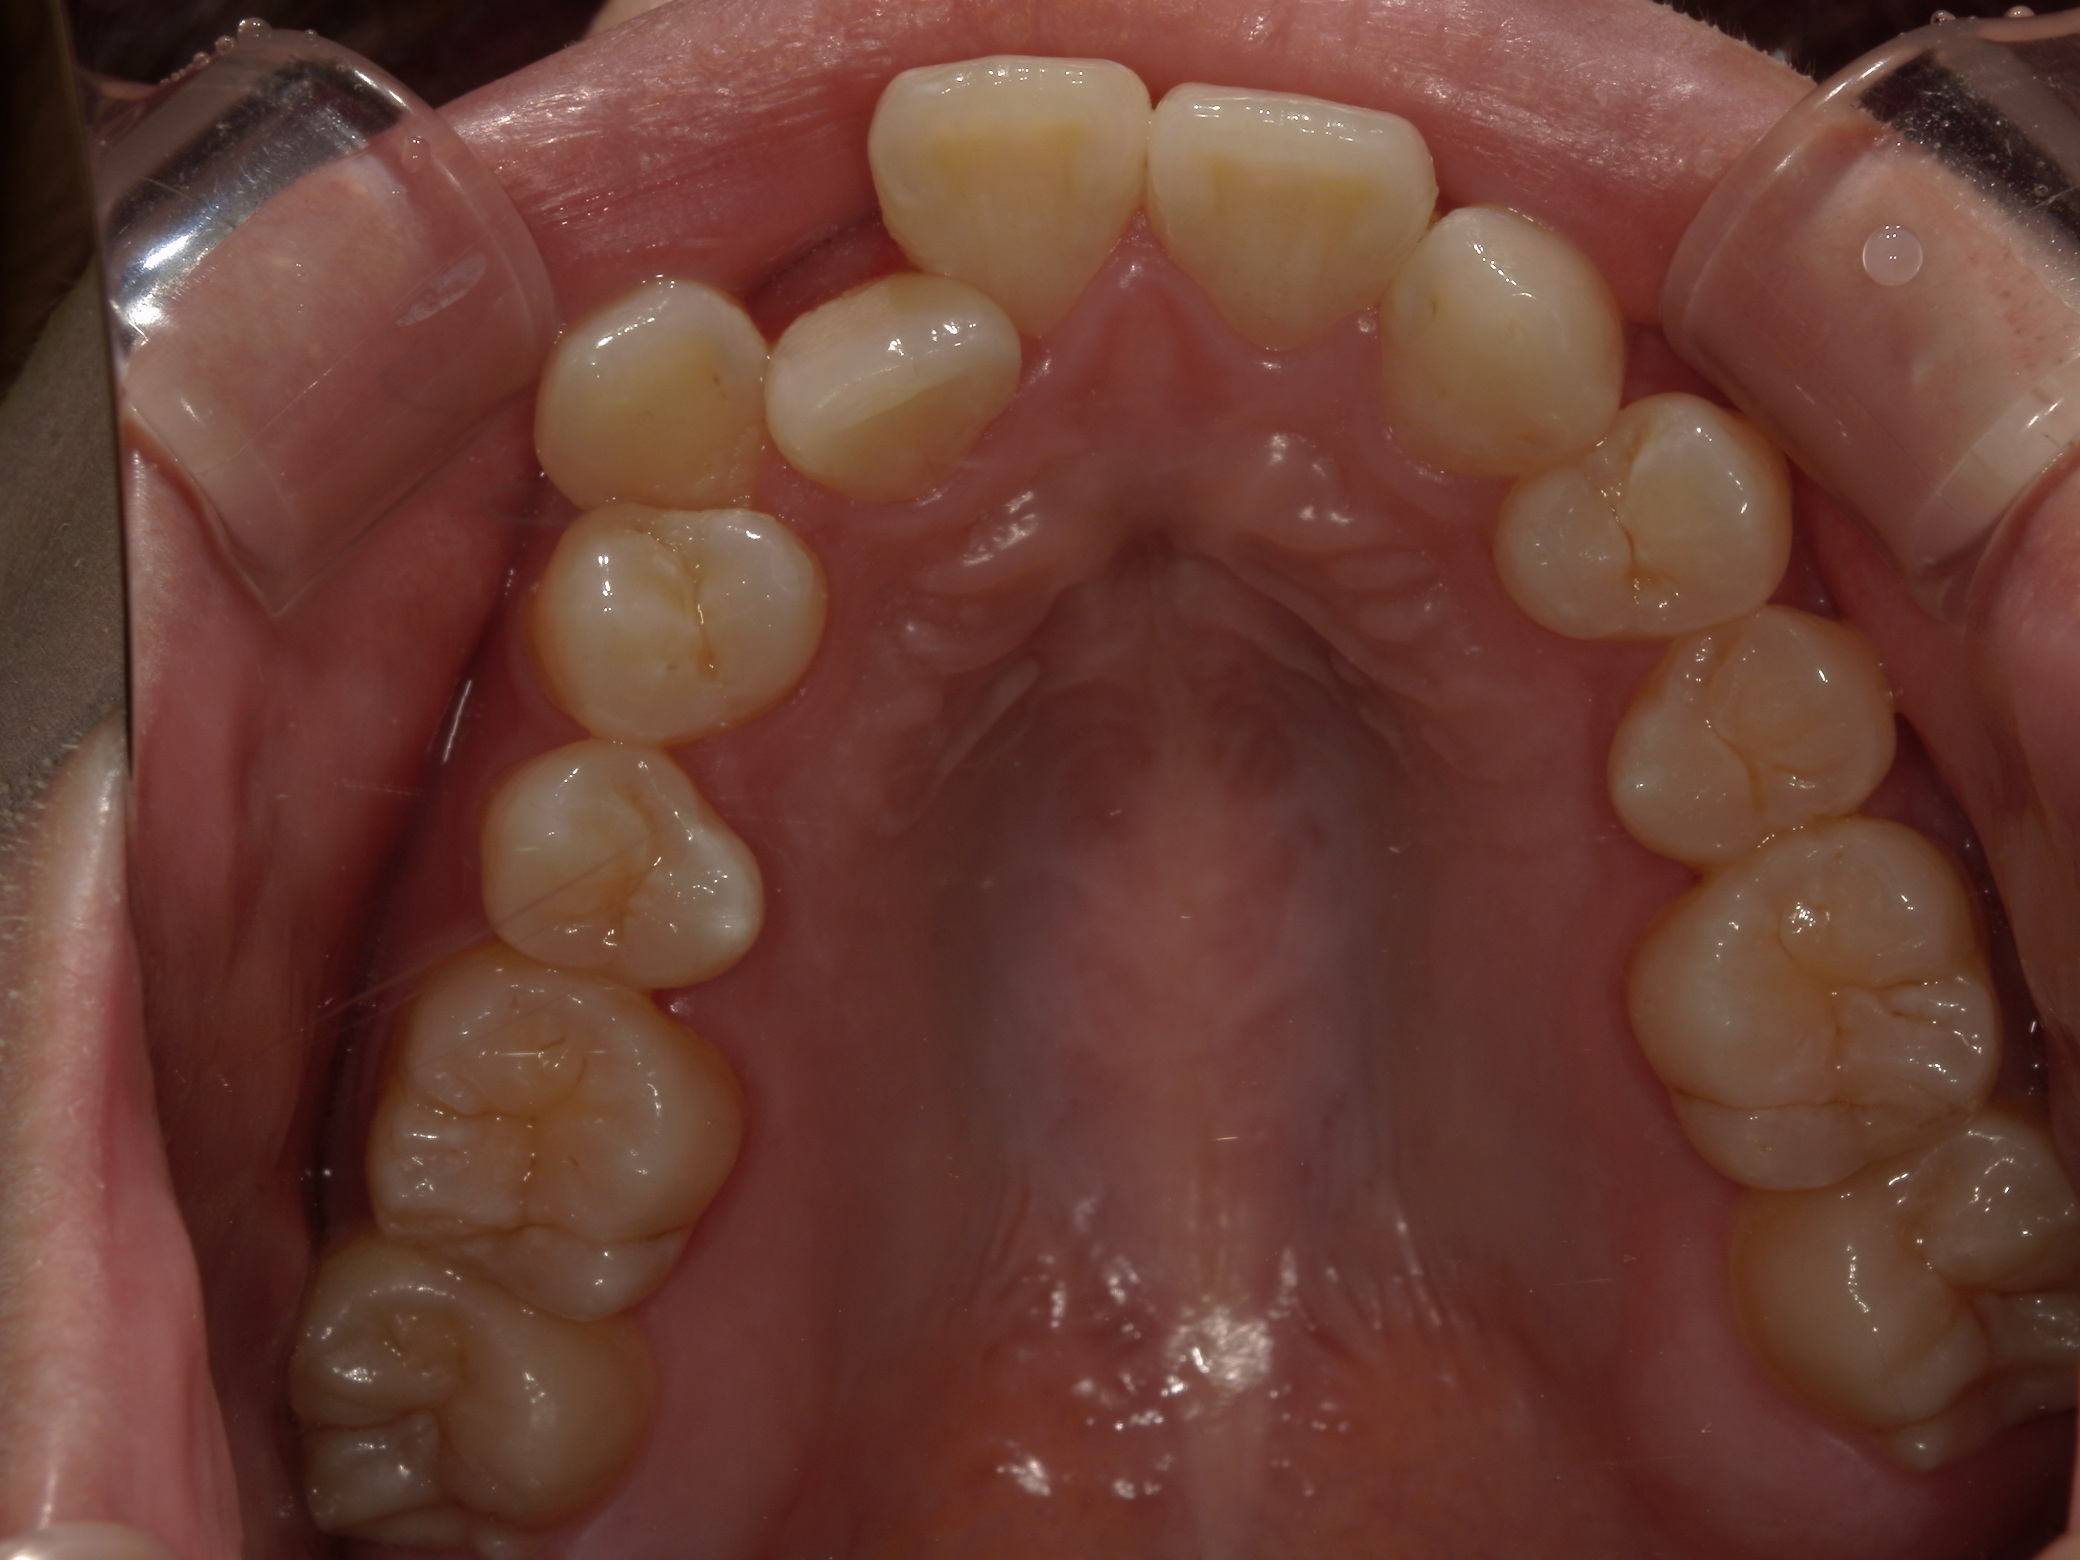

歯並びの乱れ(叢生)が気になる

| 年齢・性別 | – |

|---|---|

| 主訴 | 歯並びの乱れ(叢生)を気にされて来院された。咬み合わせや審美的な改善を希望されていました。 |

| 治療期間・回数 | 3年・28回 |

| 費用 | 840,000円 |